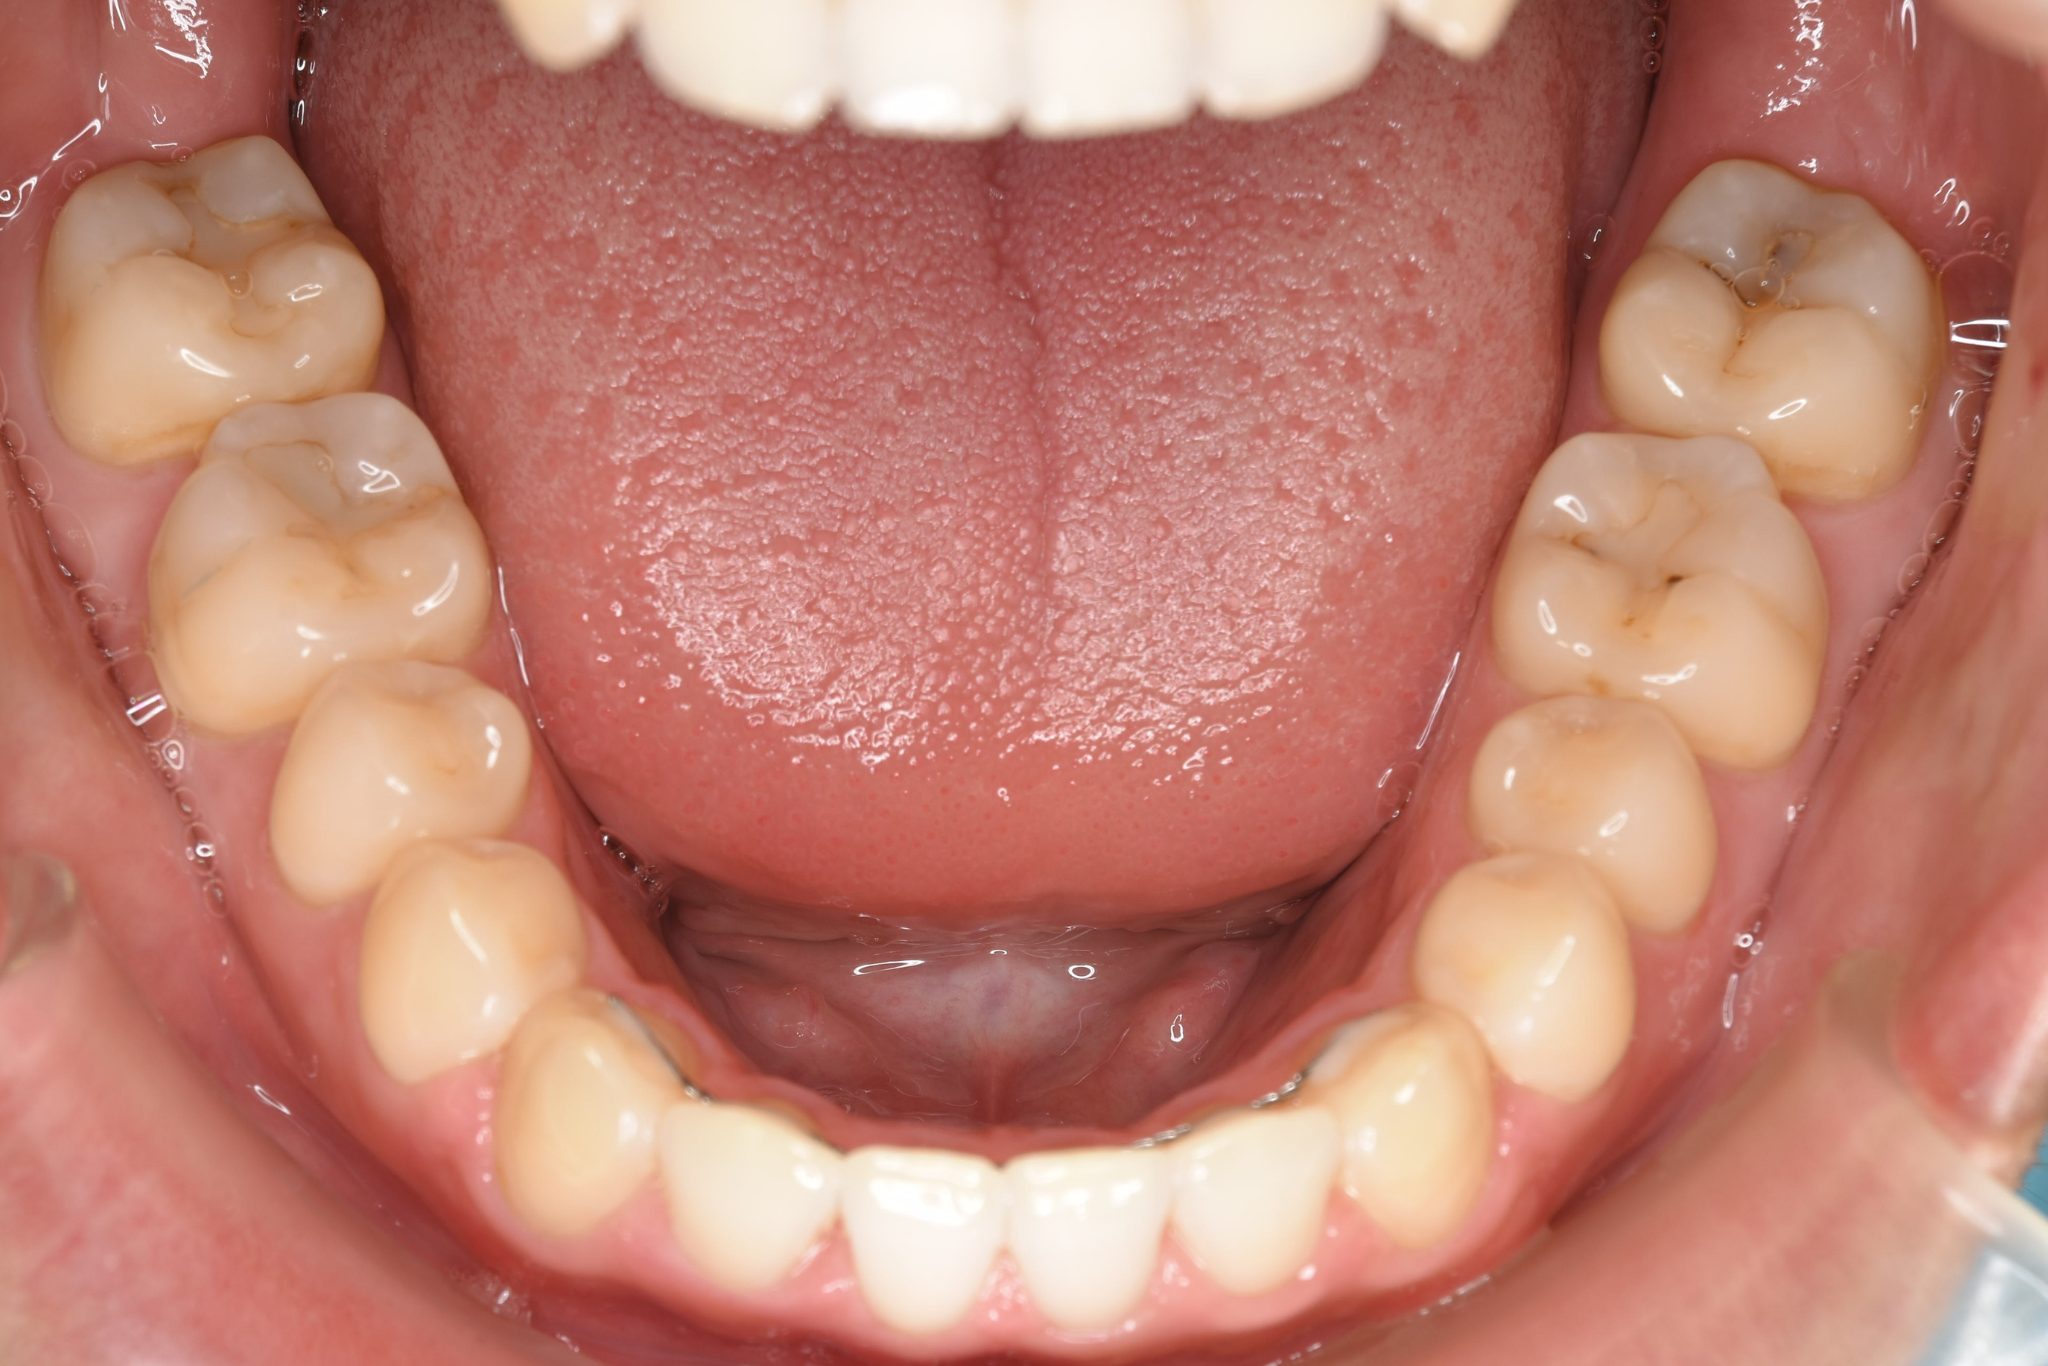

ビフォー

ワイヤー矯正治療|症例_495